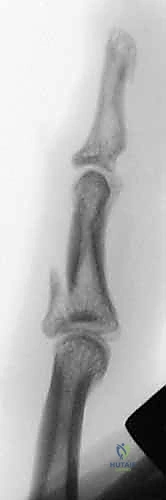

Figure 1C (TECH FIG 1C) confirms the wire inserted across the head of the proximal phalanx, verified on the image intensifier, before further advancement.

- Finalize Proximal Wire Placement: Once confirmed, advance the wire fully through the bone, ensuring equal lengths are present on either side of the finger. This symmetry, while less critical for the proximal wire, will serve as a useful guide for balancing the distal wire later.

Initial Distal Wire Insertion: Similar to the proximal wire, insert the 1.1-mm K-wire percutaneously, aiming for the center of the middle phalanx. This wire must be perpendicular to the long axis of the finger and, crucially, parallel to both the plane of rotation of the PIP joint and the previously inserted proximal wire. This parallelism is essential for creating a functional dynamic construct.

-

Fluoroscopic Confirmation (Partial Insertion): Insert the wire partially through the middle phalanx and check its position carefully with both PA and lateral views on the image intensifier.

*Figures 1F and 1G (TECH FIG 1F,G) confirm the insertion and position of the distal wire on the image intens